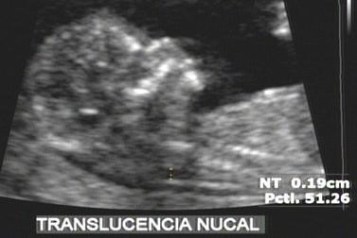

O exame deve ser realizado em datas específicas da gestação, para obtenção dos melhores parâmetros para avaliação da gestação; assim o morfológico de primeiro trimestre deve ser realizado entre 11 e 13 6/7 semanas, para avaliação da translucência nucal, ducto venoso, osso nasal, para rastreamento das cromossomopatias e cardiopatias no primeiro trimestre, assim como malformações estruturais demonstráveis neste período da gestação.